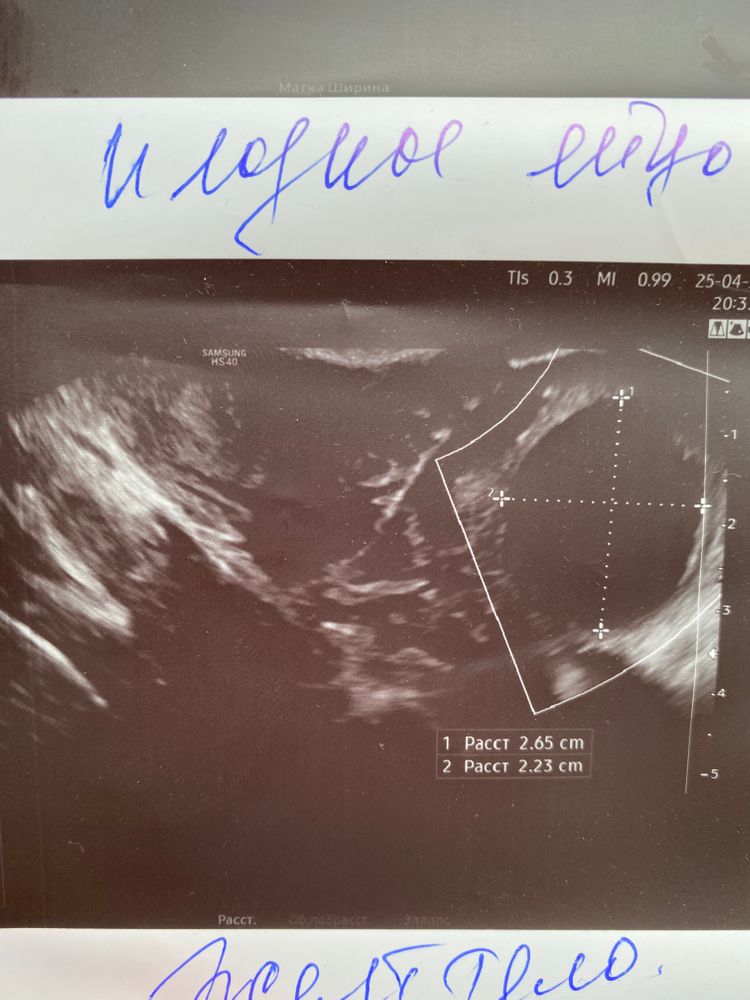

УЗИ И ПЯ ИЛИ ЧТО 😤

Знаете, лично я не вижу ЖТ, но вижу фоликулярную кисту или просто большой ДФ. ПЯ не вижу, просто может быть узелок, полипчик, складка, пузырёк воздуха, сгусток кровки и др.

УЗИ и беременность Фолликулометрия у разных врачей